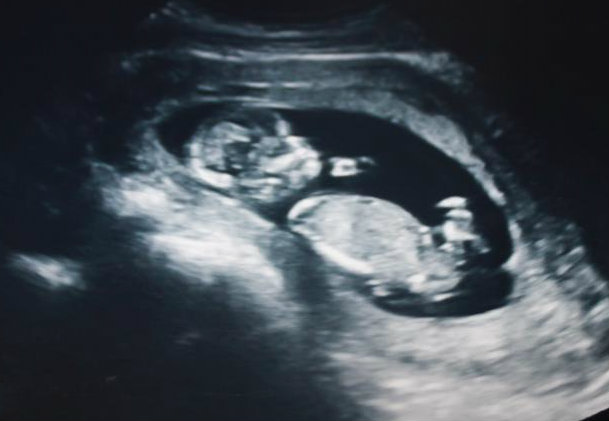

13 week ultrasound - can you see a nub? Lovemy4, please help! :)

I had an ultrasound yesterday at 12 weeks 5 days. Baby was measuring 13 weeks 3 days. Heart rate was 167. Baby was moving around a lot and I'm not sure if I ever saw a clear nub at all. :( I did see a potty shot and didn't see anything protruding between the legs at all, I saw what looked like a white spot between the legs (didn't see three lines, but wondering if it may have been girly parts seen from a distance, it wasn't a very close-up shot). My symptoms this pregnancy have been identical to my previous girl pregnancy. I don't have a gender preference, but this just feels like a girl to me. Any thoughts? If the nub isn't visible, what do you think based on skull shape? I thought the profile reminded me of my daughter, she had a rounded forehead like this, and my son's was very straight.